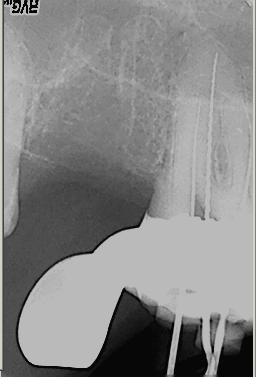

Röntgenologischer Ausgangsbefund im Febr. 2003 mit caries profunda, starken Krümmungen sowohl der mesiobuccalen wie auch der distobuccalen Wurzeln

Zustand unmittelbar vor Behandlungsbeginn im Juni 2003. Die Fraktur des distalen Zahnanteils hat die Patientin jetzt zur Einwilligung in die Behandlung motiviert. Auffällig ist in dieser Projektion die besonders starke Krümmung der mb Wurzel sowie die knochennahe Defektlage distal. Es erfolgte zunächst die Kariesentfernung gefolgt von einer chirurgischen Kronenverlängerung zur Herstellung der biologischen Breite sowie Ermöglichung des sog. Ferrule-Effektes. Danach wurde der Zahn adhäsiv aufgebaut. Erst jetzt wurde mit der eigentlichen WKB begonnen